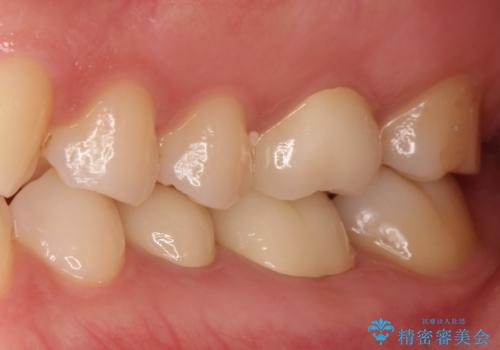

【メタルフリー】銀歯を白くしたい。オールセラミッククラウン。

- 銀歯を白くしたいと希望され来院されました。

すぐにでも白くしたいとのことで、2回目の来院で銀歯を白い仮歯に変更し喜んでいただきました。

ただ単純に白くするでけではなく拡大鏡を使用し、丁寧な処置を行なっております。